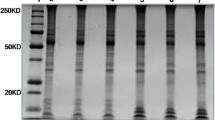

SDS-PAGE/ In-gel Trypsin Digestion

Frozen tissue lysates were thawed briefly, resuspended in SDS-PAGE sample buffer and run for a short distance (0.5 cm) onto pre-cast NUPAGE (Thermo Fisher Scientific) 1-D SDS gels. Gels were stained with Colloidal Blue (Thermo Fisher Scientific) and the entire 0.5 cm stained gel region was excised and digested overnight using 20 ng/ml modified trypsin, as previously described [14].